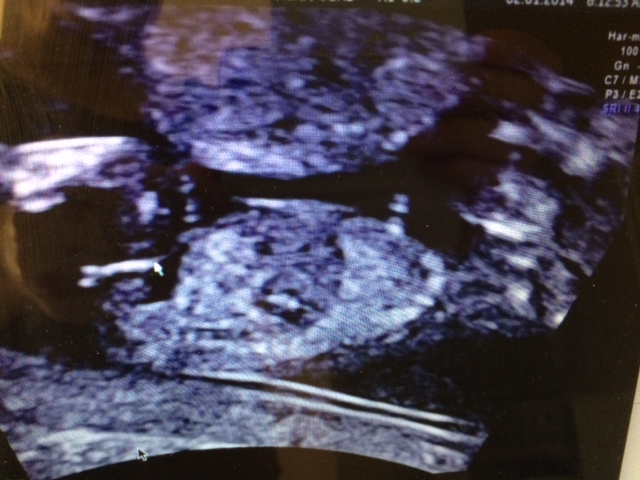

Had my 12 week 5 day scan today and a nice clear pic of the nub, whats your gender guess for my little one?

And does anyone know how accurate the nub method is?

Girl and it is 85% accurate I do believe. You are close to 13 weeks and there is no rise I would be surprised if it is a boy .

Very girly nub!!! Congrats!

At 13 weeks...pretty darn accurate. Especially with that nub. Very girly! Would also be shocked if it were a boy.

Looks girly to me

Looks like a girl to me too - congrats!

girl